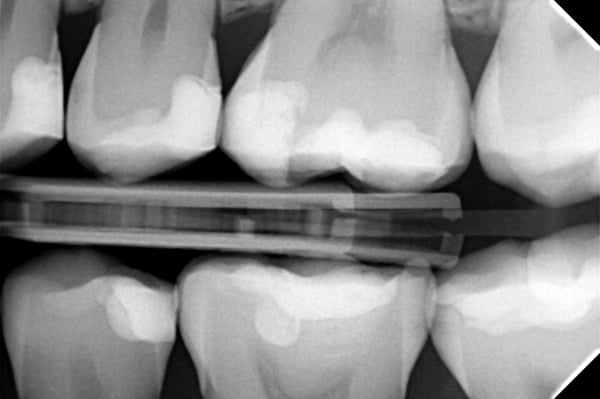

Na het polijsten kreeg de vulling een verzegeling (PermaSeal™-composietsealer, Ultradent Products). Tot slot werd de occlusie gecontroleerd en werden röntgenopnamen gemaakt.

Zoals te zien is op de foto’s van het eindresultaat, zorgt Transcend-composiet voor een zeer esthetische restauratie. Het sectionele matrixsysteem Halo leverde een uitstekende approximale anatomie, wat bleek uit de röntgenopname.